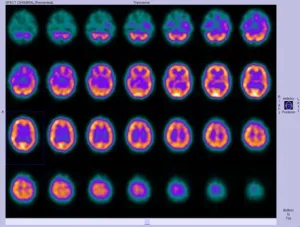

If you or someone you care for has ever wrestled with unexplained neurological symptoms—whether it’s memory fog, MS flare-ups, or Parkinson’s challenges—this matters. But we’re not just talking about “seeing” the brain. We’re talking about seeing what’s happening in it. That’s where the concept of a PET tracer brain inflammation imaging comes into play.

Enter 2024-2025. Now, we’ve got PET tracer brain inflammation tools that walk into a sci-fi movie. Things like [18F]-T-401 and [11C]-MC1. Why does that matter? Let’s keep this simple: we’re not just guessing anymore. We’re actually seeing inflammation flicker and map it across the brain with more detail—and precision—than ever before. You can almost hear it saying, “Look, I’m doing something important in here!”

The nitty-gritty’s not as complicated as it sounds: the 18F or 11C tag in the tracer attaches to proteins like TSPO or MAGL found on inflamed cells. The PET scanner captures tomography snapshots—kinda like a photo album of your brain’s “hot spots.” Think of it as a spotlight falling on troublemakers. According to a paper from Technology Networks, this has opened the door for evaluating neuroinflammation in Alzheimer’s, Parkinson’s, and even depression. Freaky cool, huh?